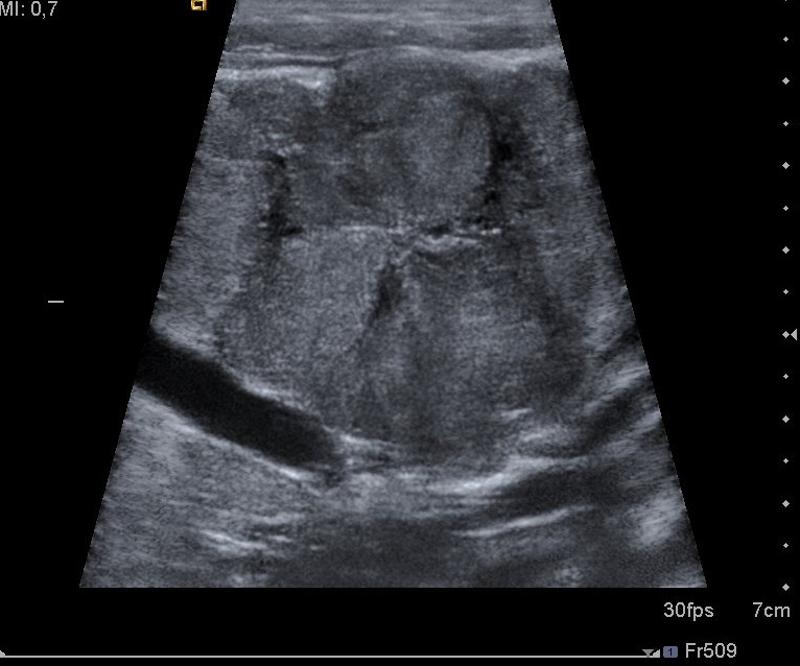

rectal bleeding

Intussception

vomiting

abdominal pain

rectal bleeding

Intussception